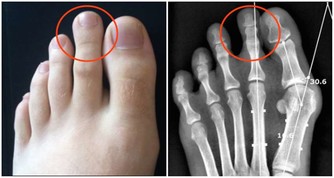

圖片翻攝自:果殼小組以及博才網 一名30多歲電腦工程師日前連續腹瀉1個月、每天拉肚子3至6次,體重狂降5公斤,檢查感染阿米巴原蟲,醫師問診發現他腹瀉前曾吃生魚片,研判是生魚片不潔引起。若生食或飲水遭含阿米巴原蟲的糞便污染,就可能感染,醫師提醒,海鮮、燒烤類食物宜熟食,要吃生魚片則應選擇環境乾淨、衛生條件較佳的餐廳。 收治病例的新光醫院消化內科主治醫師朱光恩說,該名男病患是電腦工程師,就醫時表示,原以為只是一般腸胃炎,未料竟連續腹瀉1個月、每天拉3至6次,糞便還帶有血絲及黏液,體重更從65公斤降至60公斤。 經腸道內視鏡切片檢查發現,男子腸道黏膜有阿米巴原蟲,用藥後已緩解腹瀉症狀。由於男子腹瀉前曾吃生魚片,朱光恩懷疑應是生魚片遭阿米巴原蟲污染。 衛福部疾管署首席防疫醫師羅一鈞說,阿米巴原蟲感染屬第二類法定傳染病,傳染途徑為糞口傳染,若生食或飲水遭含阿米巴原蟲的糞便污染,或手、口接觸患者肛門,就有感染風險。阿米巴原蟲進入人體後,易侵犯腸、肝、肺及腦,延誤治療恐致死,全台每年約100至200名患者,其中半數為本土患者。 羅一鈞解釋,阿米巴原蟲以吞噬紅血球維生,會破壞體內微血管,侵犯腸道即會造成腸道黏膜出血而血便,侵犯肝臟會引起肝臟發炎、化膿,而有發燒、眼白變黃等症狀,嚴重會導致腹膜炎。無論淡水魚或海水魚,只要曾置於遭阿米巴原蟲污染的水中,魚體均可能帶此原蟲,羅一鈞表示,在台感染阿米巴原蟲最常見的原因,仍是廚師雙手或製作環境未注意衛生,少數為食材受污染。羅一鈞建議若要吃生魚片,應選擇環境乾淨、衛生條件較佳的餐廳,至於吃生魚片常沾的山葵,僅能增加口感、風味,並無法殺菌、消毒或殺死阿米巴原蟲的效果。 開業胃腸肝膽科醫師張振榕說,一般腸胃炎的腹瀉約持續3至7天,阿米巴原蟲感染腸道的腹瀉可長達2至4周,且糞便帶有黏液,若腹瀉逾兩周應速就醫。此外,外出旅遊或用餐宜喝瓶裝水,別喝山泉水或用山泉水洗手後進食,海鮮、燒烤類食物宜吃熟食;如廁時若曾接觸馬桶坐墊、廁所門把,應先洗淨雙手再進食。